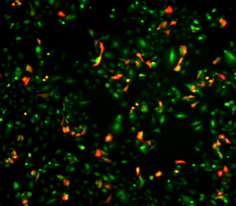

Apoptosis and Cytotoxicity. Image Credit: Scintica Instrumentation Inc.

Phagocytosis. Image Credit: Scintica Instrumentation Inc.